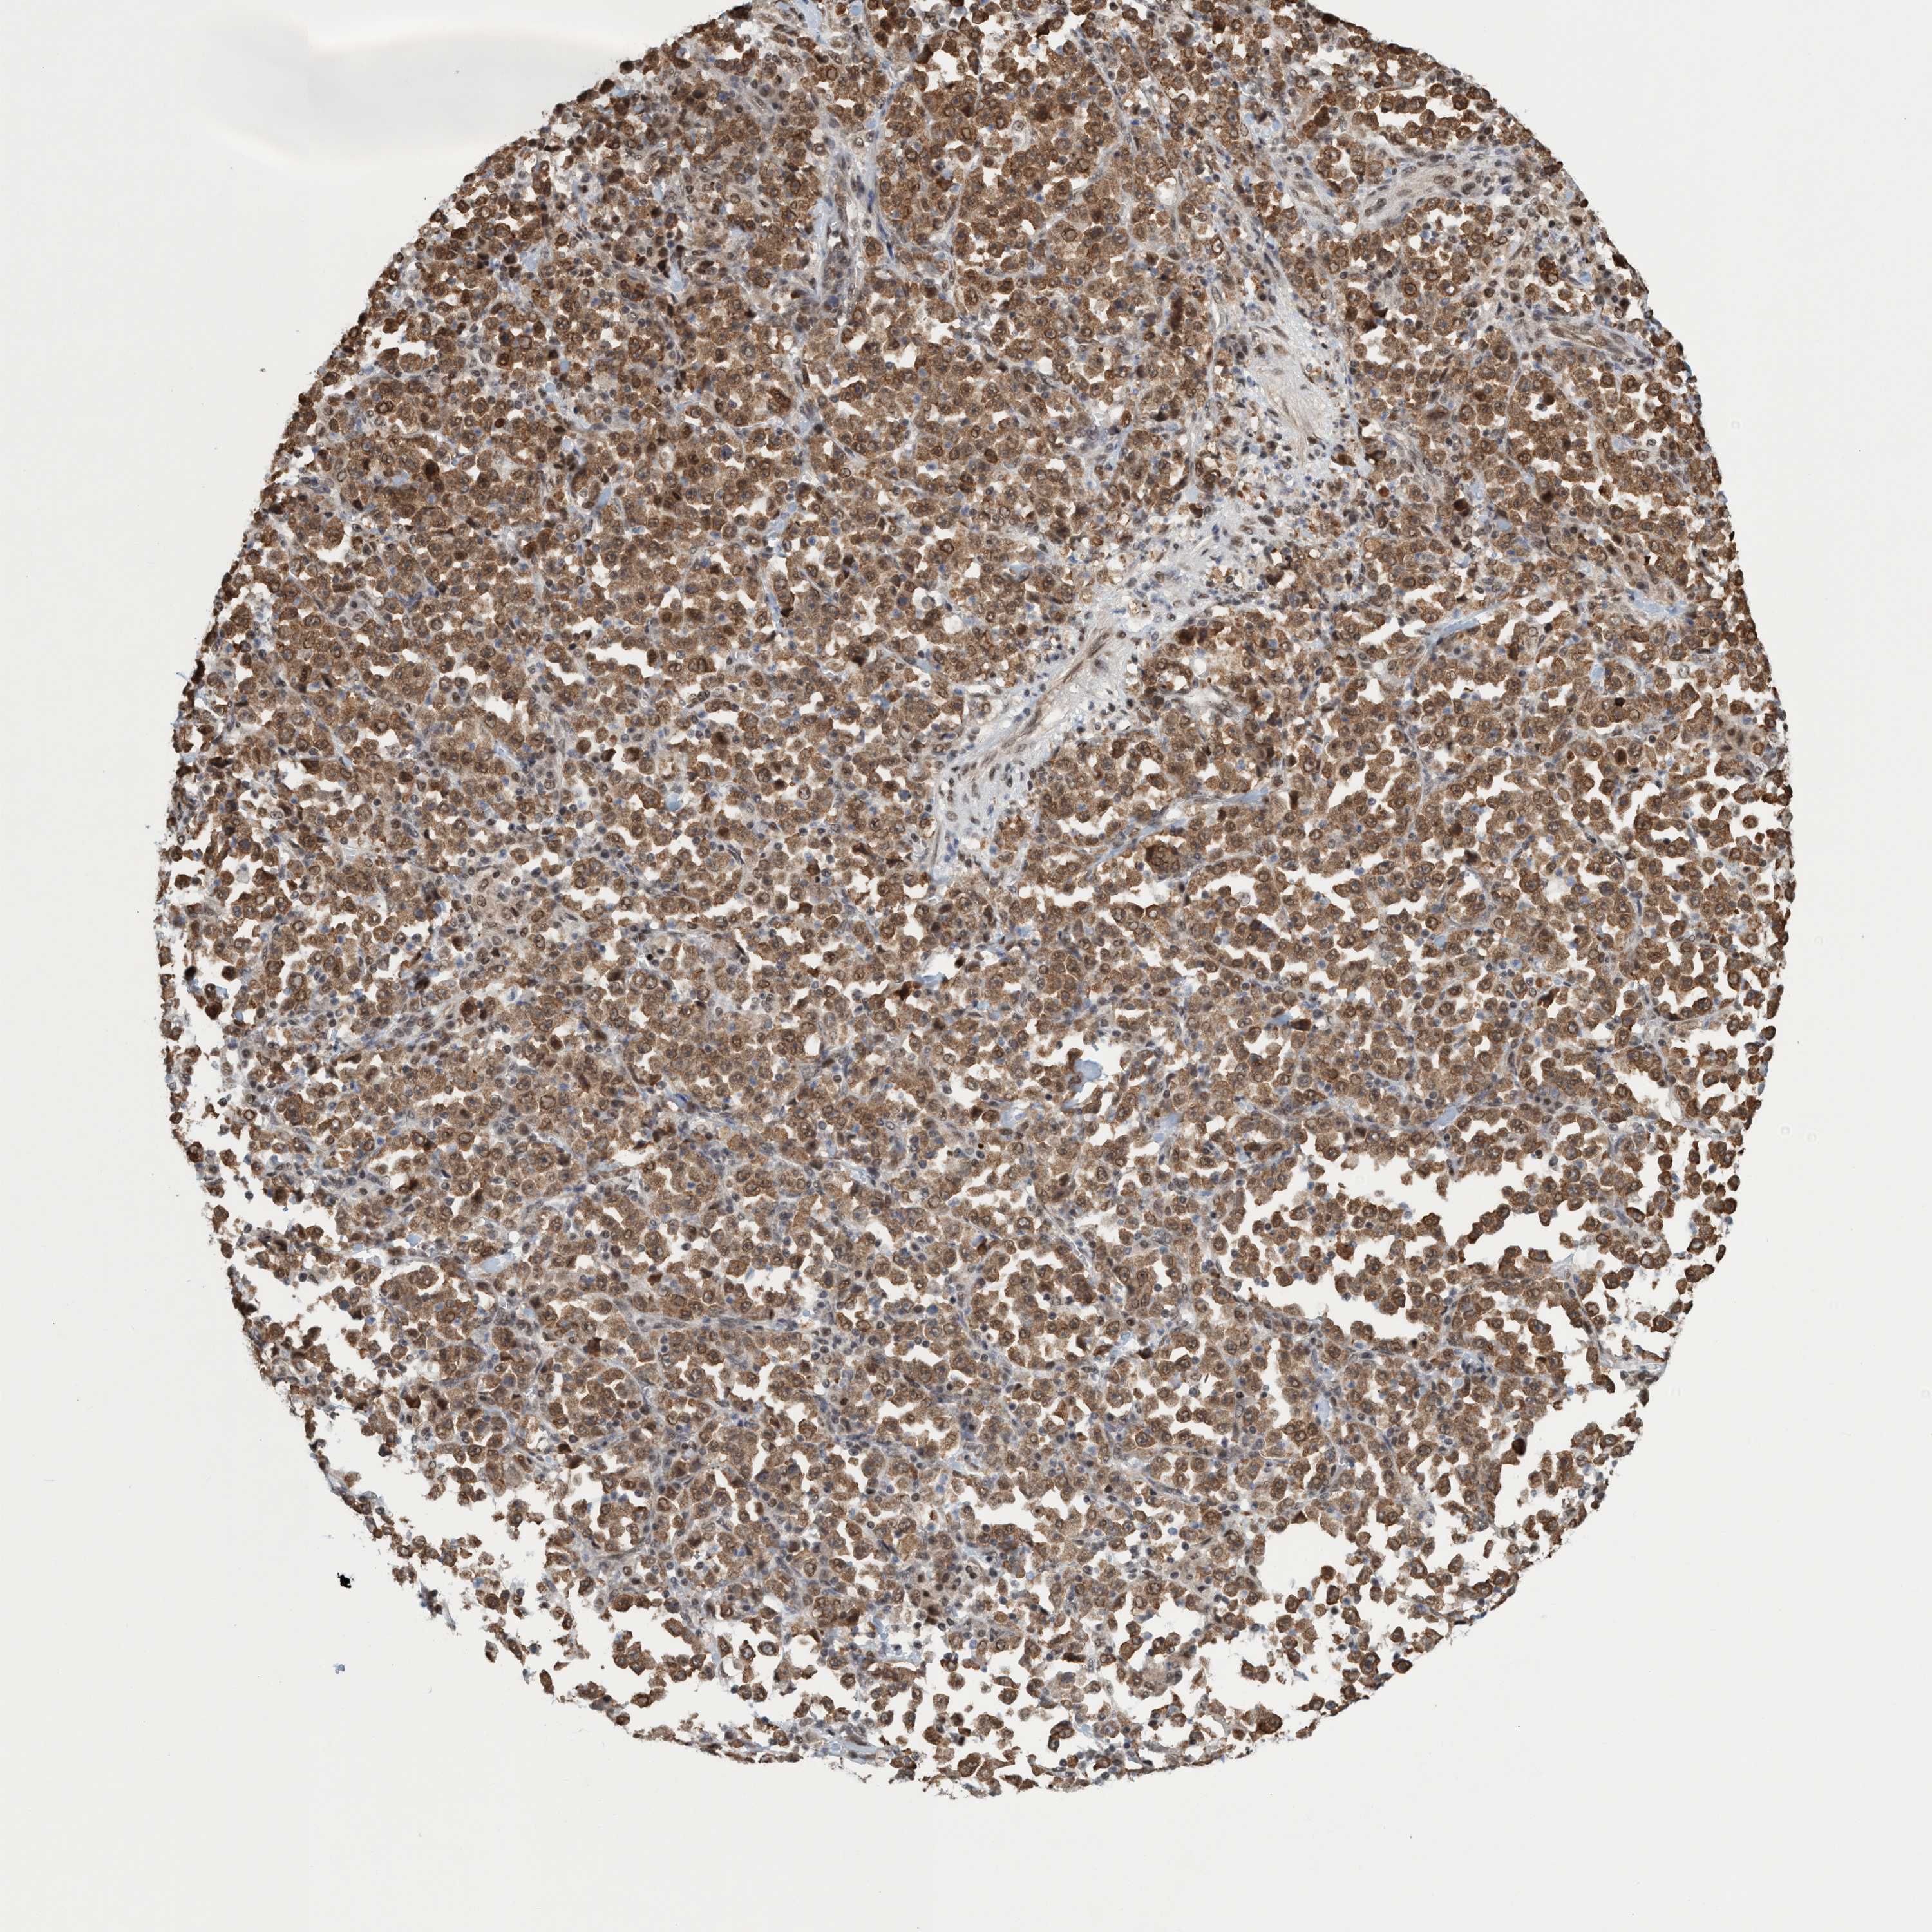

STOMACH CANCER - Protein expressioni

A mouse-over function shows sample information and annotation data. Click on an image to view it in a full screen mode. Samples can be filtered based on level of antibody staining by selecting one or several of the following categories: high, medium, low and not detected. The assay and annotation is described here.

Note that samples used for immunohistochemistry by the Human Protein Atlas do not correspond to samples in the TCGA dataset.

Antibody stainingi

Antibody staining in the annotated cell types in the current human tissue is reported as not detected, low, medium, or high, based on conventional immunohistochemistry profiling in selected tissues. This score is based on the combination of the staining intensity and fraction of stained cells.

Each image is clickable and will lead to virtual microscopy that enables deeper exploration of all samples and also displays staining intensity scores, fraction scores and subcellular localization as well as patient and tissue information for each sample.

Antibody HPA021557

Antibody HPA024646

Staining

High

Medium

Low

Not detected

Intensity

Strong

Moderate

Weak

Negative

Quantity

>75%

75%-25%

<25%

None

Location

Nuclear

Cytoplasmic/membranous

Cytoplasmic/membranous,nuclear

Adenocarcinoma, NOS